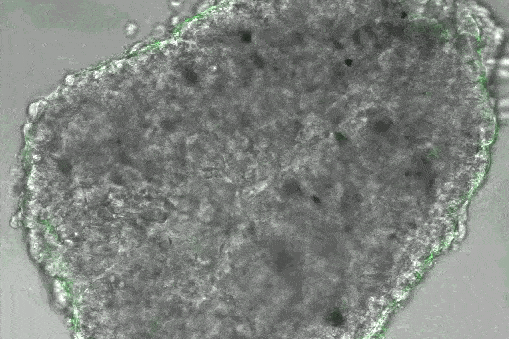

Вакцина против рака, как и прививки от коронавируса, работает на молекулярном уровне — ее относят к классу мРНК-вакцин, которые считаются более эффективными. По словам доктора медицинских наук, профессора кафедры онкологии и лучевой терапии Института хирургии Пироговского университета Елены Артамоновой, мРНК в данном случае вводится часто прямо в лимфоузел человека: там она кодирует один или несколько пептидов, обладающих высокой иммуногенностью. «Дендритные клетки захватывают мРНК, она попадает в их цитоплазму, где становится матрицей для производства антигенных пептидов, — объясняет Артамонова. — Главная роль дендритных клеток — презентация Т-лимфоцитам чужеродных пептидов, на которые необходимо „направить“ адаптивный иммунитет».

«Использование мРНК-вакцины позволяет „нагрузить“ дендритную клетку антигенными пептидами, на которые мы хотим выработать иммунный ответ. При этом удается достичь таких концентраций пептидов, каких не позволяет получить ни один другой способ вакцинации, — раскрывает особенность работы профессор Пироговского университета. — У пациента отбирают образец опухолевой ткани, идентифицируют неоантигены, которые связаны с этой опухолью. Затем происходит подготовка персонализированной мРНК-вакцины, направленной против большого числа (до 34) высокоиммуногенных неоантигенов, характерных для конкретной опухоли конкретного пациента».